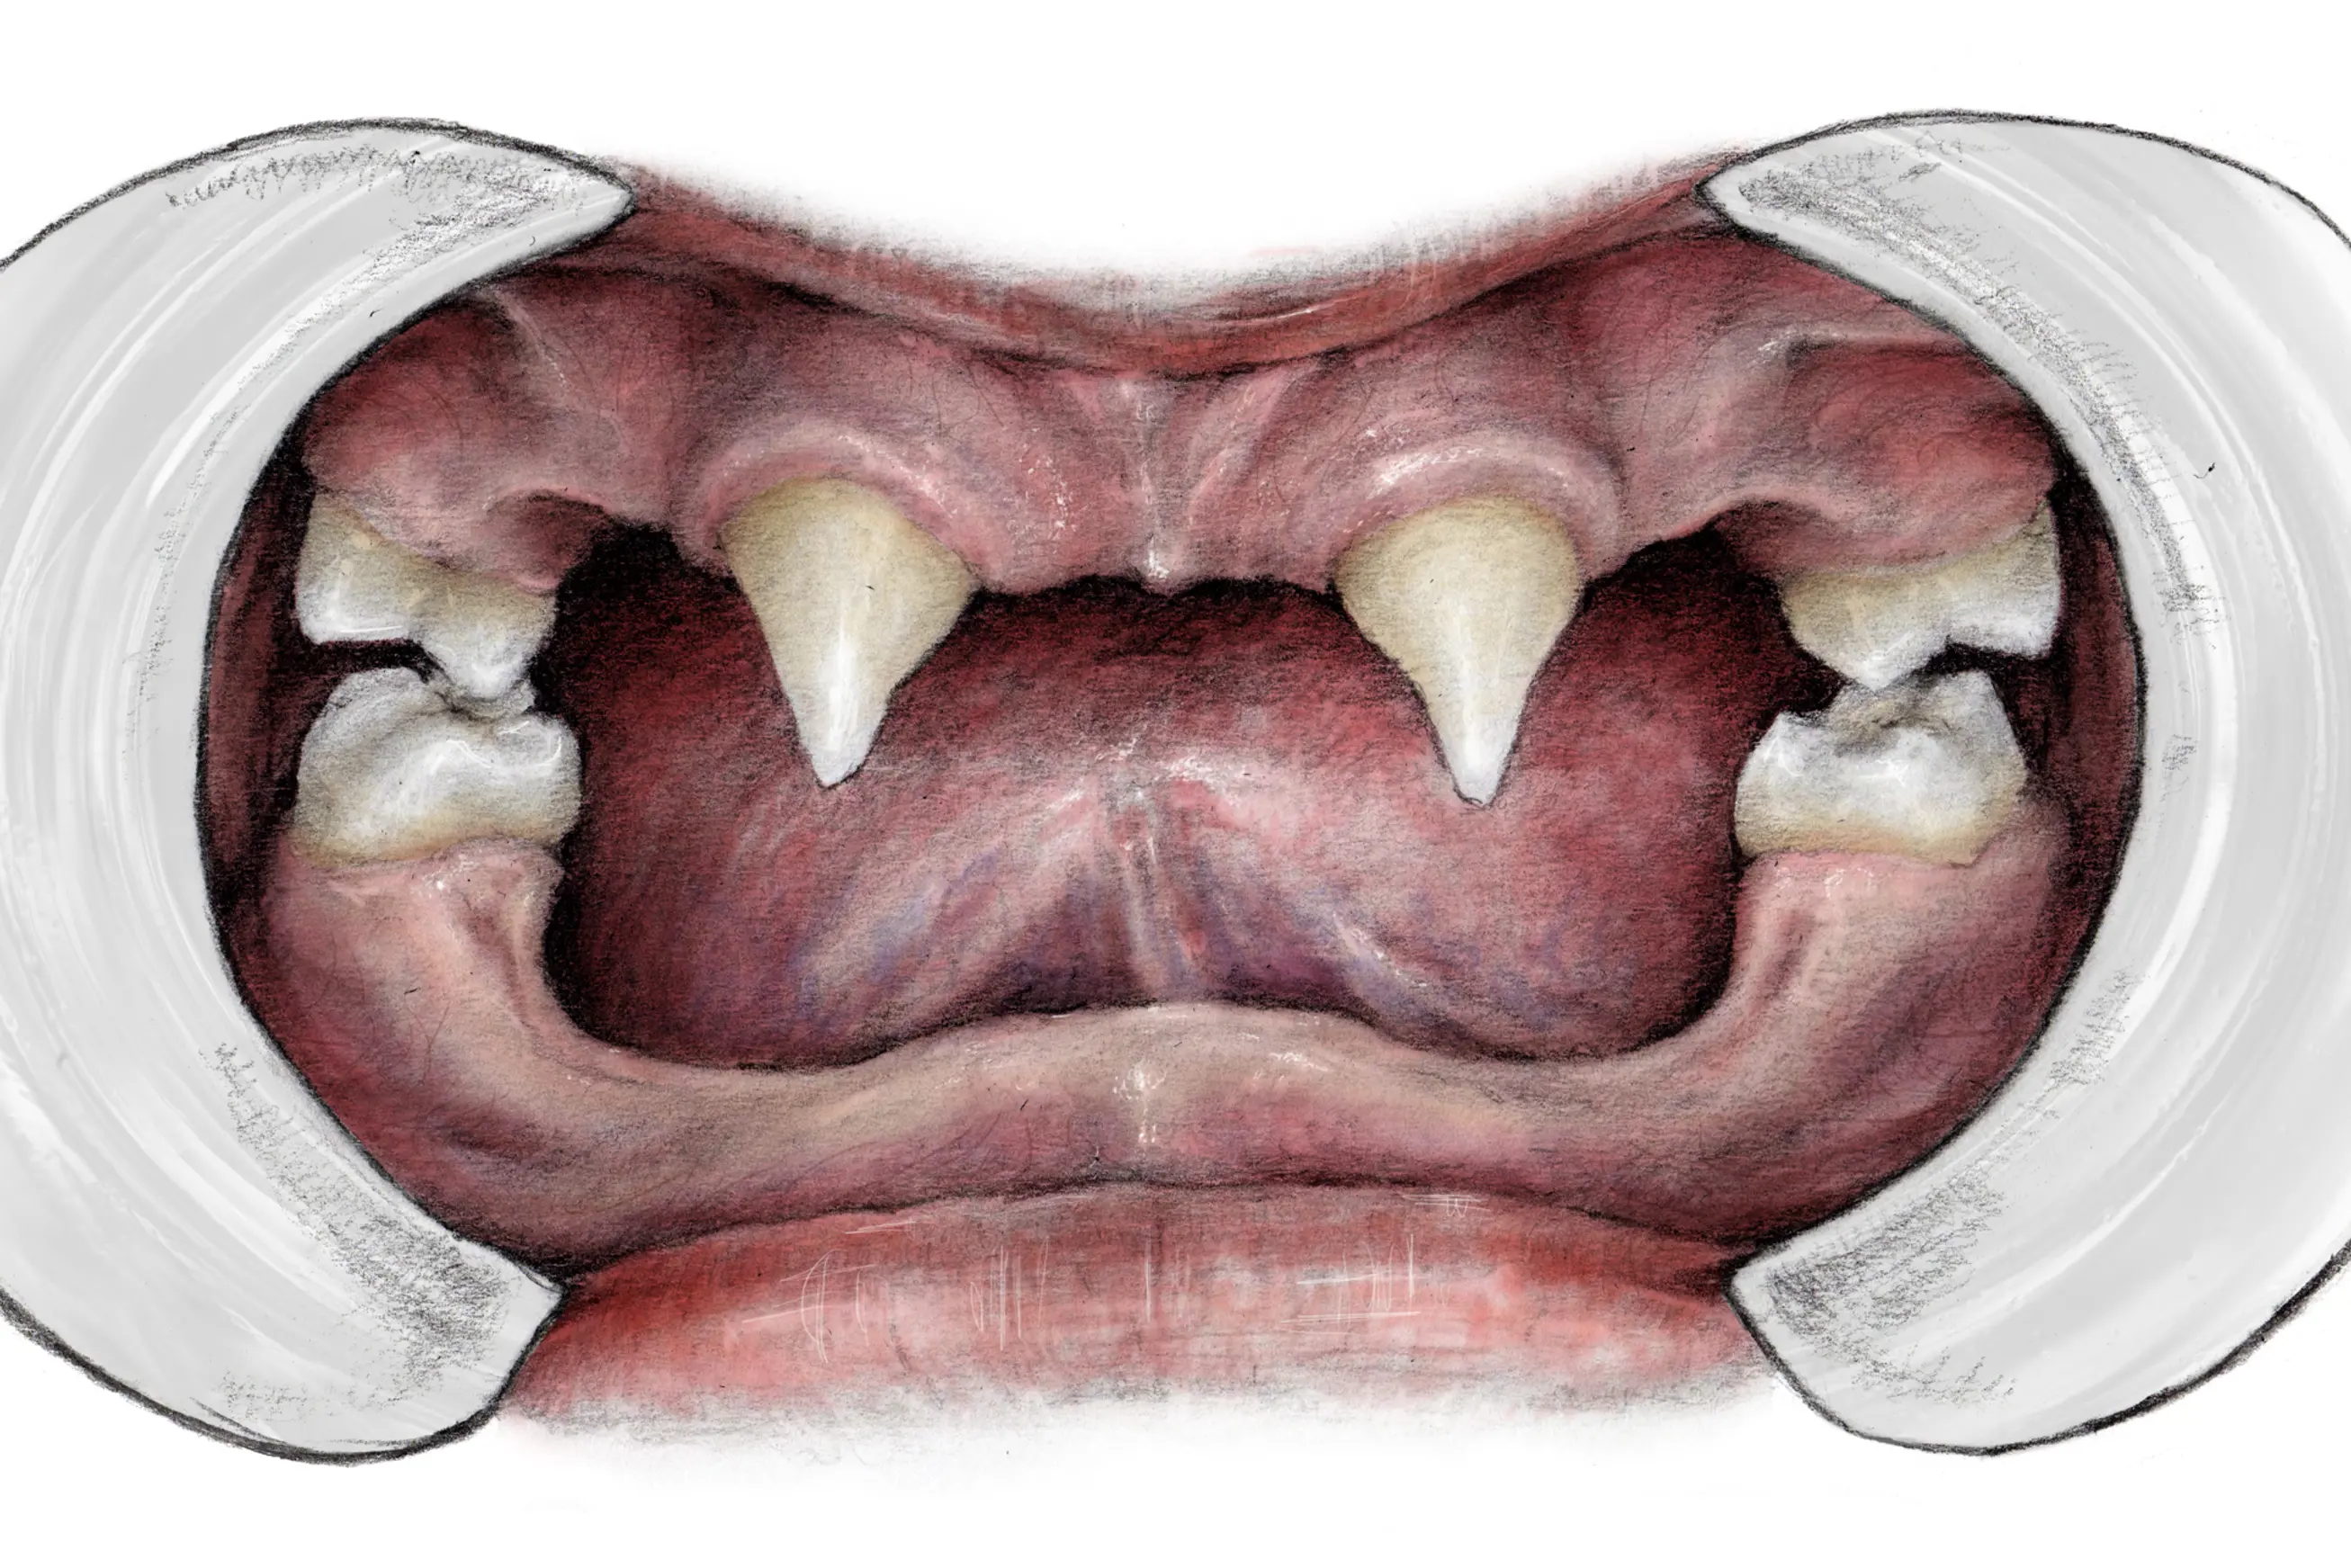

Å mangle seks tenner eller flere kalles oligodonti. Av de som har HED har 60-80 prosent oligodonti, sammenlignet med 0,08-0,5 prosent i normalbefolkningen. I gjennomsnitt dannes og utvikles ni tenner; vanligvis tennene i fronten og første jeksel. Variasjonen er imidlertid betydelig. Gutter med X-bundet HED utvikler et fåtall tenner. Hos jenter er det først og fremst det permanente (blivende) tannsettet som berøres, og i mye mindre grad enn hos gutter. Selv innen samme familie kan antallet manglende tenner variere mye hos hver enkelt med HED. De tennene som hyppigst utvikles er hjørnetenner og seksårsjeksler. Total mangel på tenner kalles anodonti. Oligodonti som isolert trekk er i seks av ti tilfeller ikke tilknyttet et spesifikt syndrom.

Gutter med HED utvikler ofte bare noen av de permanente tennene, spesielt tenner i fronten og første molar (jeksel). Illustratør: Malin Bernas-Theisen, TAKO-senteret.

Tannform

Fortenner er ofte karakteristisk koniske (spisse). Dette er også et vanlig trekk i familier med et arvelig manglende tannanlegg uten syndromtilknytning. Fortennene er generelt betydelig smalere enn gjennomsnittet, gutter er i større grad berørt enn jenter.